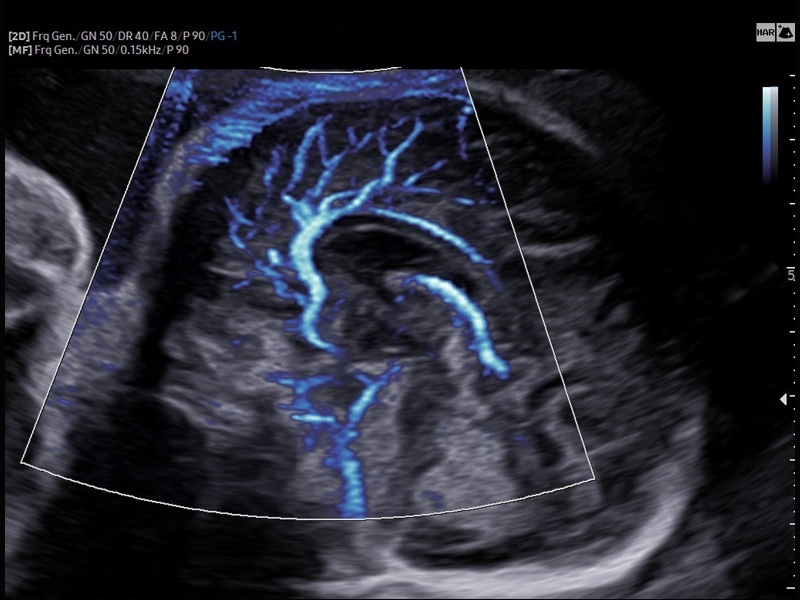

• Акушерство и гинекология

• Модуль5D CNS– программа автоматического построения основных срезов головного мозга плода в режиме объемного сканирования.

• Модуль5D HeartColor – программа автоматического построения основных срезов средца плода в режиме объемного сканирования с анализом кровотока.

• МодульCrystal Vue- программа реконструкции прозрачного 3D УЗИ, которое получается при одновременном усилении внутренних и наружных структур. Применяется для визуальной оценки состояния плода и матки, помогает лучше идентифицировать мягкие ткани и кости.

• Модуль Crystal Vue Flow- программа реконструкции прозрачного 3D УЗИ, которое получается при одновременном усилении внутренних и наружных структур. Применяется для визуальной оценки состояния плода и матки, помогает лучше идентифицировать мягкие ткани и кости. Так же визуализирует объемный кровоток.

• Модуль MV-Flow – программа (режим), позволяющая визуализировать кровоток в микроциркуляторном русле с высоким разрешением без использования контраста.

• Модуль LumiFlow – программа отображения кровотока с объемной графикой для лучшего понимания архитектоники сосудистого русла.

• СистемаLive 3D- трехмерное сканирование объемными датчиками в реальном масштабе времени (4D).